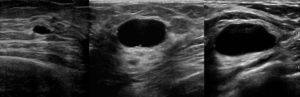

- Ультразвуковое исследование. Информативный метод, позволяющий определить наличие, локализацию и размеры кисты. На УЗИ легко определяется качество стенок опухоли и её возможные осложнения. Специальной подготовки к такому исследованию не требуется.

- УЗИ. Данный вид исследований используется для уточнения диагноза, полученного при помощи маммографии. Посредством ультразвукового исследования определяют размер и степень разрастания новообразования.